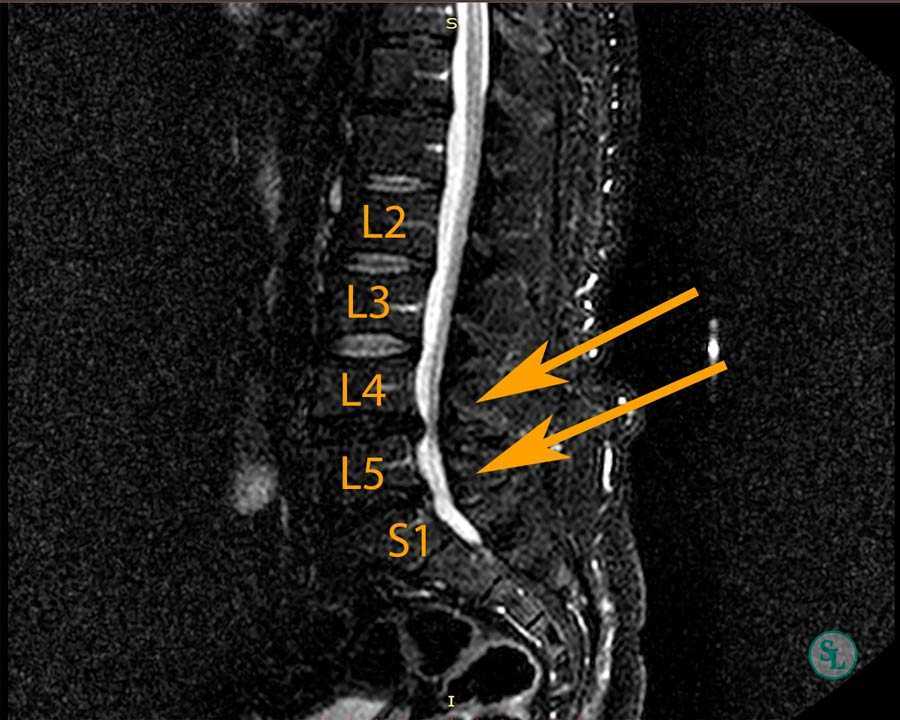

Мрт картина дегенеративно дистрофических изменений пояснично крестцового отдела позвоночника